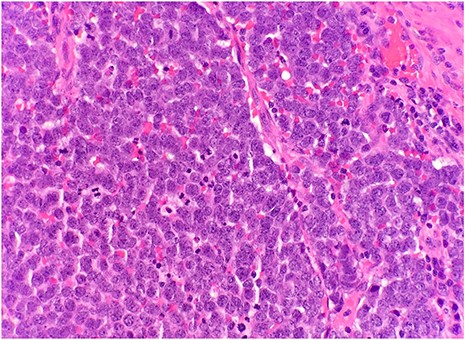

After surgical excision, specimen was received by pathology in formalin and consisted of a fragment of pink-tan dense tissue measuring 6.5 × 5.5 × 4 cm. The cut section revealed a fresh and necrotic surface. Microscopic examination revealed nests of monotonous round tumor cells with infiltration of the subcutis. Tumor cells had a scant eosinophilic cytoplasmic rim and round, vesicular nuclei with abundant mitotic figures (Fig. 1) and neuroendocrine features (CD56 and Synaptophysin positive) (Fig. 2). Immunohistochemical stain CK20 demonstrated paranuclear dot-like staining, consistent with MCC (Fig. 3). Negative staining for CD45 excluded lymphoma. The tumor demonstrated positive margins with vascular invasion.

Microscopic examination reveals nests of monotonous round tumor cells. Tumor cells have scant eosinophilic cytoplasmic rim, round and vesicular nuclei with abundant mitotic figures (HE × 20).